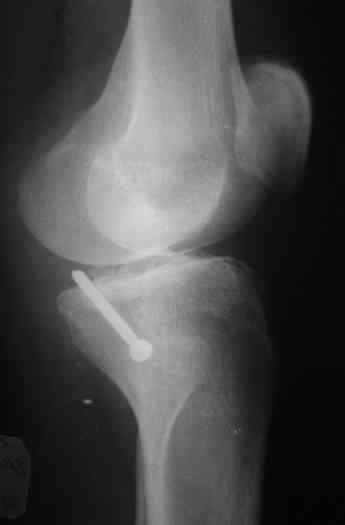

В 3 из 4 случаев мы применили винт, проведенный ретроградно по аналогии с фиксацией заднего края большеберцовой кости при переломах в

области голеностопного сустава. В прищепке рентгенограммы одного из наших пациентов до операции и спустя полгода. Остальные 3 наблюдения

описаны в статье "Изолированный отрывной перелом большеберцовой кости в месте прикрепления задней крестообразной связки // Вестник

травматологии и ортопедии им. Приорова. - 2001. - №1. – С. 38-40. Если есть интерес, могу прислать копию. Ваш случай, безуловно, отличается величиной костного фрагмента, его локализацией, характером и степенью смещения. Но думаю, принцип лечения может быть общим.